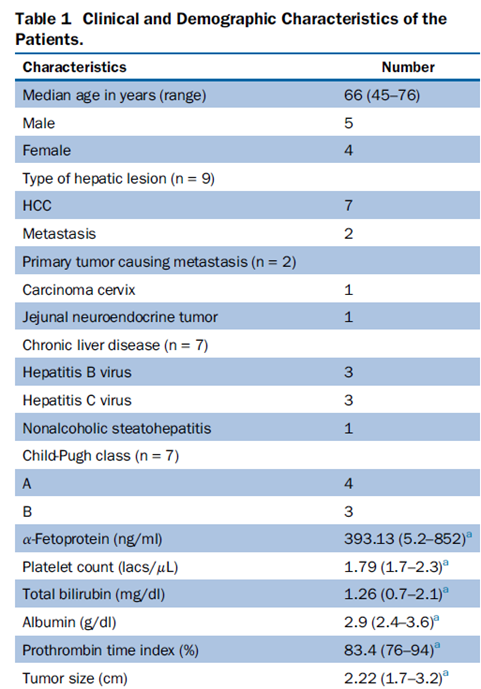

冷冻消融胆囊附近肿瘤病灶

(A)动脉期 MRI 显示胆囊附近有外周增强病变(箭头)。

(B)手术过程中 CT 显示冷冻探针位于病灶内。

(C)消融后,术后 1 个月CT 显示完全消融(箭头)。